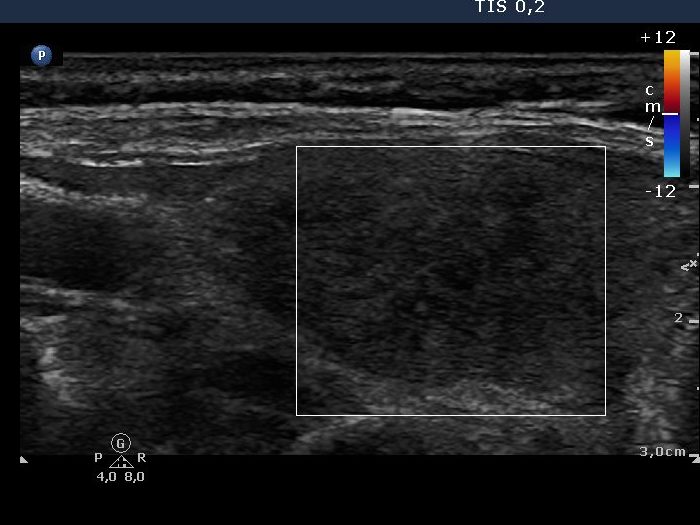

Right lobe, longitudinal scan

Right lobe, longitudinal scan, color Doppler mode. The lobe is avascular.